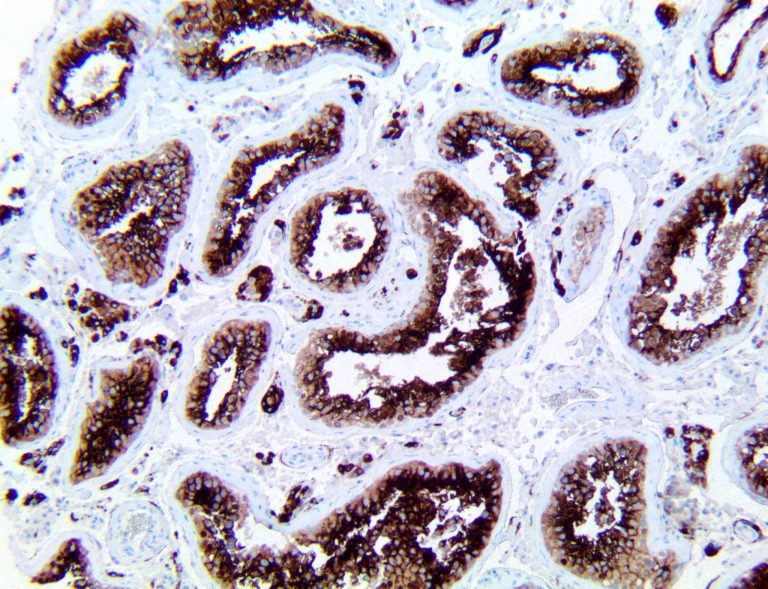

The first cytokines released are interleukin 1β (IL-1β) and tumor necrosis factor-α (TNF-α), which attract a variety of circulating white blood cells (WBCs) to the infection site, including neutrophils, monocytes, macrophages, and natural killer (NK) cells. This response, along with the antipathogenic chemicals released by these cells (i.e., complement), comprise the innate immune response. These cells directly attack the invading pathogen and also release additional cytokines, chief among them interleukin-1 and 6 (IL-6). IL-6 is essential for invoking the adaptive immune response, which calls T-cells, B-cells, and T helper (Th) cells to the infection site. IL-6 also stimulates further recruitment, proliferation and activation of macrophages.

This activation induces inflammatory monocytes to highly express IL-6, starting a localized and then systemic cascade effect that results in hyperproduction of IL-6, which accelerates the inflammatory process. Because IL-6 also increases vascular permeability, excessive levels cause blood vessels to become very leaky. This, along with clotting factors released from vascular endothelial cells, stimulates the coagulation cascade, resulting in microthrombosis (tiny clots), which leads to ischemia and tissue death of the kidney, intestines, heart, liver, brain and extremities.